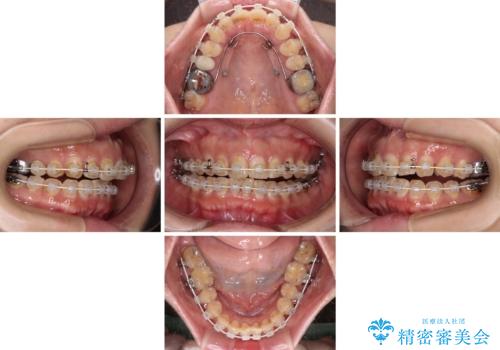

なるべく早めに治療を終えたいとのことで、補助装置を用いて上顎臼歯を後方に移動させ、同時にワイヤー装置にて整えることとしました。

舌の突出癖が原因で上下の歯に大きなスペースが生じていたため、舌のトレーニングをしっかり行っていただくことで、上顎歯列をスムーズに移動させることができました。